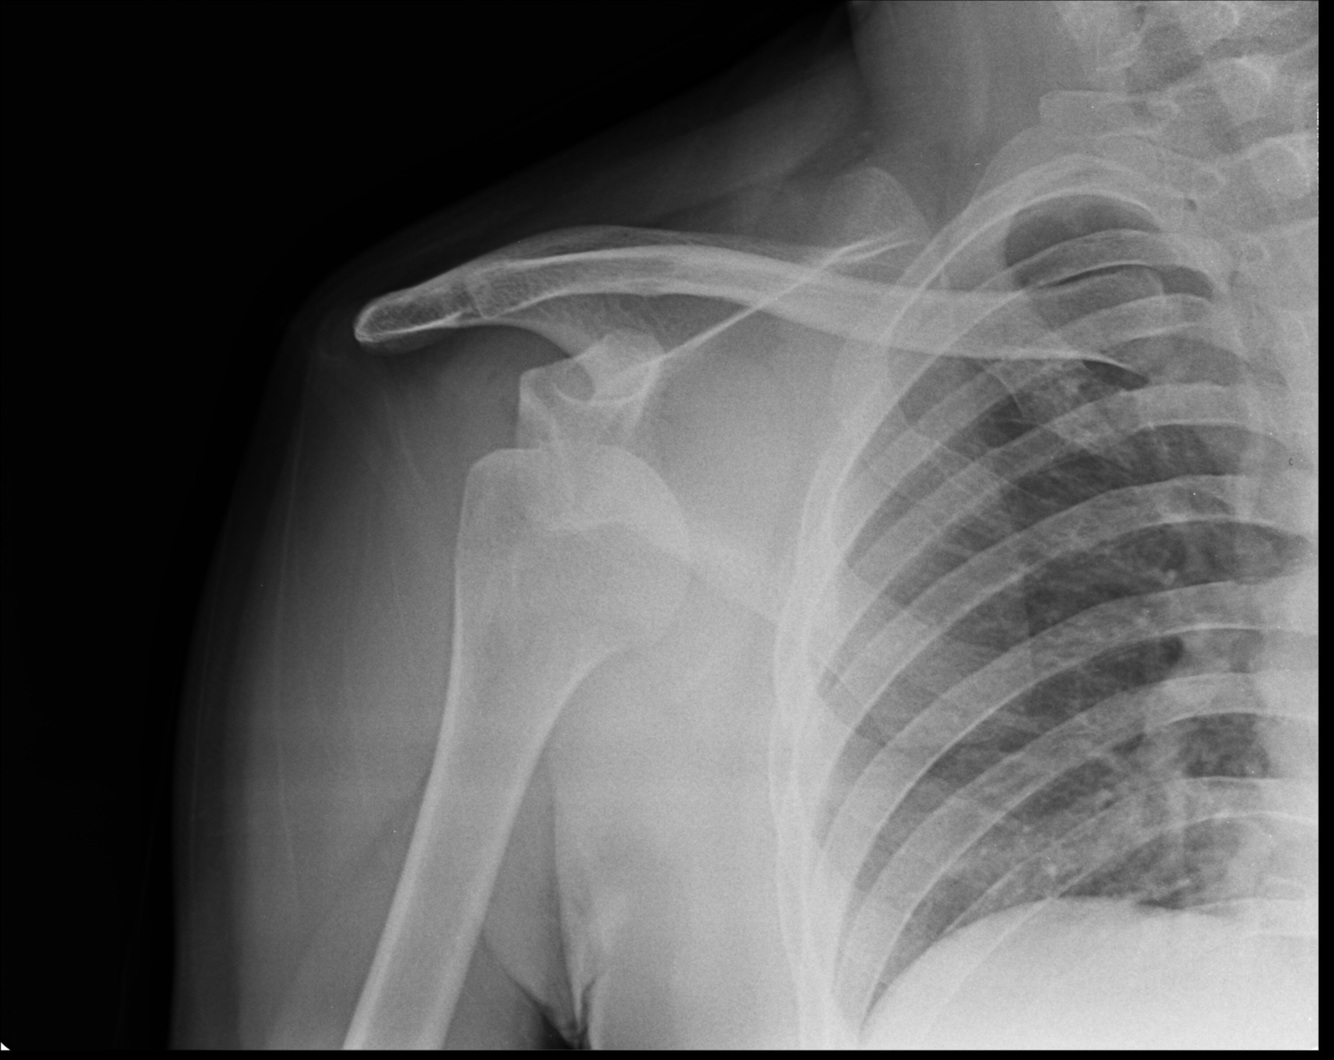

Loss of contour of normally rounded shoulder. What condition do you suspect

dislocation of shoulder

Examination reveals this. What do you suspect